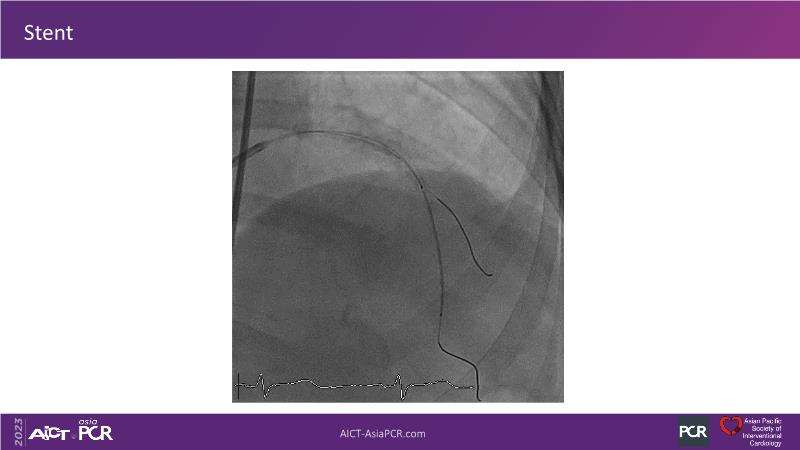

• To see advantages of RotaCUT as part of lesion preparation in left main bifurcation